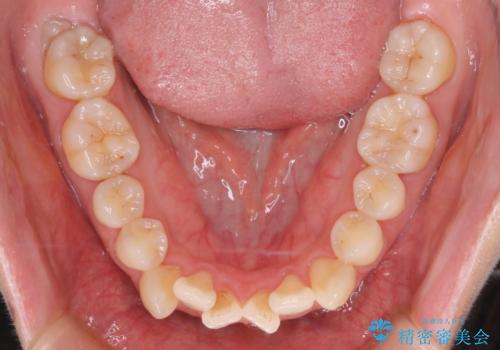

【審美装置】前歯のデコボコを綺麗に

- 上の前歯のデコボコが気になるということで来院されました。

叢生量(デコボコ)が多いため、上下左右4番目の歯を抜歯してワイヤー矯正を行う治療計画を立てました。

主訴である前歯のデコボコが改善され、噛みあわせも綺麗になりました。

歯肉退縮もなく、予定通りに治療を終えることができ良かったです。